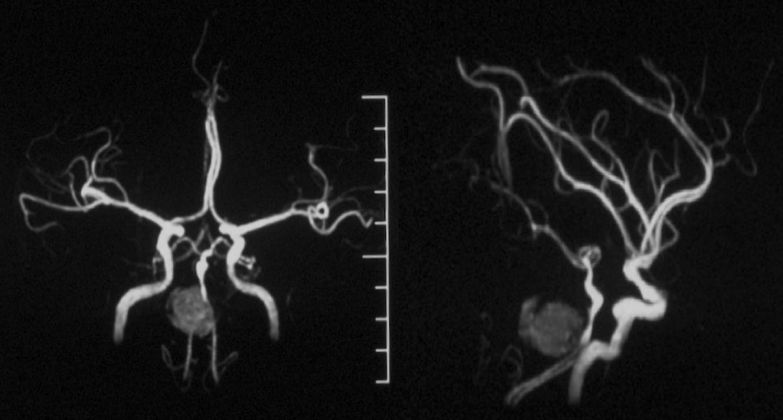

本院DSA:基底动脉巨大夹层动脉瘤,双侧后交通动脉未见明显开放(图6)。

图6

本院 DSA三维血管重建(2019-10-10)显示:基底动脉巨大夹层动脉瘤(图7)。

图7